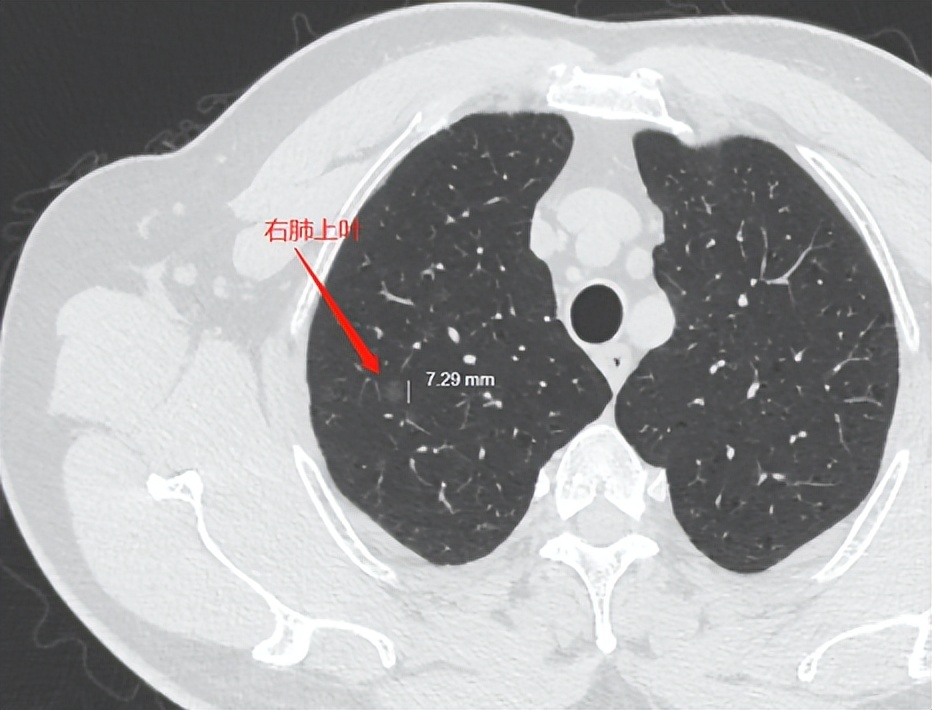

病患情况:40余年吸烟史,Ⅱ型糖尿病,2022年2月体检发现右肺上叶可见斑点状、磨玻璃样高密度结节灶,左侧主支气管内可见结节灶,直径约0.8cm(4月份支气管镜检测为鳞癌),2022年4月因咳嗽住院,经过胸部CT(128肺+心脏)检测,右肺上叶散在少许斑片状磨玻璃结节灶,边缘模糊。左肺下页支气管开口区见结节状软组织密度灶。经过支气管镜取病理检测,确诊为乳头状鳞状细胞癌(非角化)。

2022年4月底我们在省会肿瘤医院进行了住院检查(CT胸部平扫+增强),发现右肺上叶尖段见磨玻璃结节,大小为8mm*7mm,CT值为-738.4HU,左肺下叶外基段见5mm*5mm小磨玻璃结节,CT值为-679.2HU(该结节已被手术切除)。之后做过PET-CT检查显示未转移。主治大夫确定手术方案为袖状切除肺左下叶,目前我父亲已做完手术出院恢复,病理结果显示低分化乳头状鳞状细胞癌,出院诊断为左肺下叶癌(PT1AN0M0),区域淋巴结状态:支气管周(0/1),7组(0/2),9组(0/1),10组(0/1),11组(0/3),我申请做了肿瘤8基因检测(实测51种基因)和PD-L1伴随诊断检测,目前结果未出。

术后由于实在不放心,我在肿瘤医院挂了肺小结节多学科门诊,几位专家诊断为AIS,要求6个月后随访。由于刚做完手术除了定期检查,未做化疗及其他辅助治疗的手段。所以想咨询下戴主任。

右侧磨玻璃结节,介于非典型增生到原位之间,还非常安全,5年内应该没有危险,安心随,不长大不管。